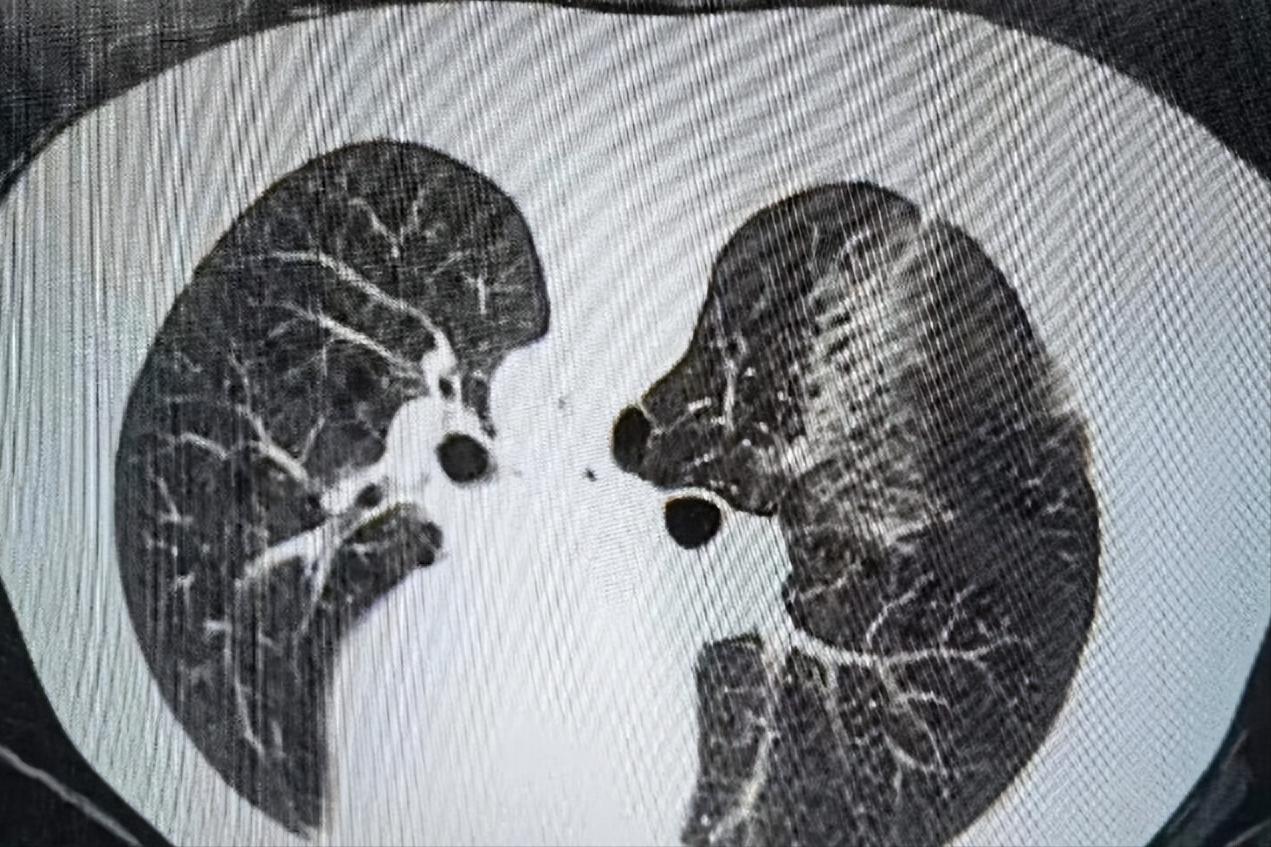

穿刺活检后:

考虑到患者高龄,长期吸烟史,肺大疱,反复自发性气胸,肺功能差,难以行外科手术切除。应急总医院呼吸与危重症医学科主任周云芝带领团队综合分析患者病情,运用当今先进的多技术综合诊疗技术,为该患者制定了“一次性”诊疗方案——经皮同轴套管肺穿刺活检+微波消融术。

一次穿刺即能活检又能消融结节,微创操作,损伤小,减少因多次穿刺引起患者不适及并发症的发生。